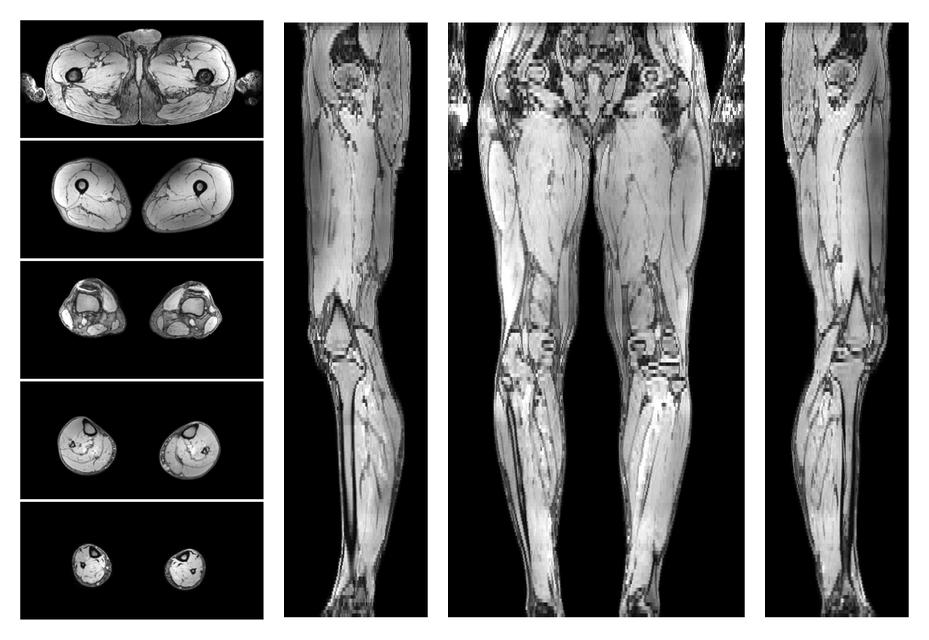

• Water only signal

The water part of the acquired multi-echo spin echo data.